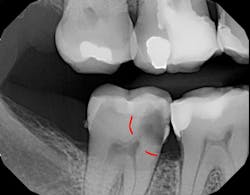

Figure 1 shows a large radiolucency on the mesial and a small radiolucency on the occlusal of tooth 31. Figure 2 shows an initial caries lesion on the distal pit and a leaking occlusal composite. Tooth 31 was sensitive to cold but normal to chewing, bite, and heat. Selective caries removal was used to prevent pulp exposure and preserve the marginal ridge.